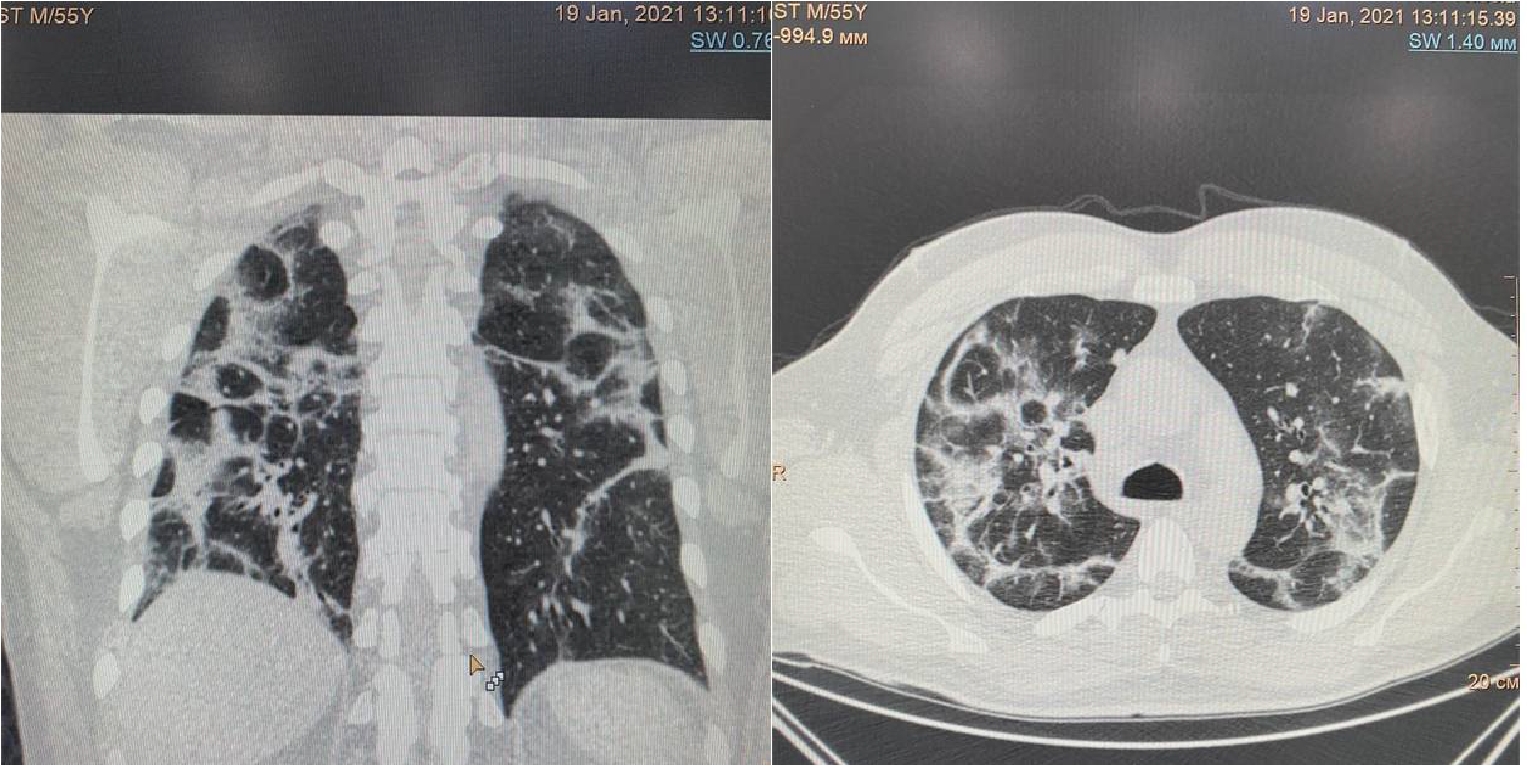

На 16 сутки госпитализации пациент начал жаловаться на резкое усиление одышки даже в покое, невозможность находиться в прон-позиции. МСКТ органов грудной клетки обнаружила уменьшение объема поражения легких до 30%, также был впервые выявлен спонтанный средний правосторонний пневмоторакс (рис. 3).

Рисунок 3. МСКТ органов грудной клетки – признаки двусторонней полисегментарной интерстициальной пневмонии (объем поражения 30%, КТ-2). Средний правосторонний пневмоторакс (красные стрелки).

Появлению данного осложнения не предшествовали какие-либо инвазивные манипуляции в области дыхательных путей, пищевода, пациент не находился ИВЛ. Однако возникновение ПТ коррелирует усугублением дыхательной недостаточности, снижением SpO2 (рис. 4) с пиком ЛДГ (до 397 ед/л), уровень которого прогрессивно возрастал на протяжении всего лечения (рис. 5).